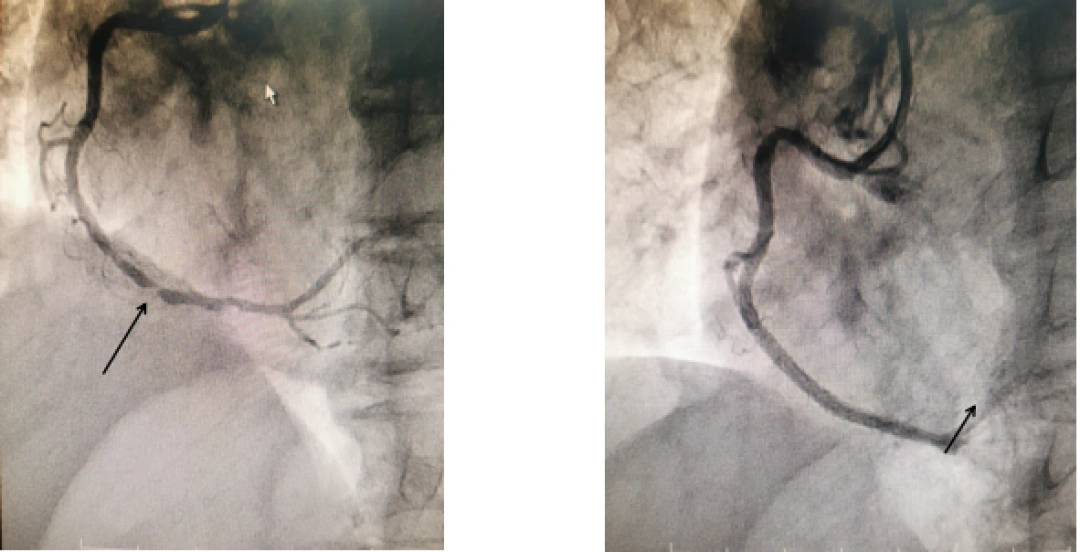

心血管内科一区副主任艾旗与李爷爷及其家属充分告知病情,同时给予患者双联抗血小板药物的预处理及对症治疗,并进行急诊介入谈话,患者及家属同意急诊介入治疗。造影结果显示患者左侧前降支近段弥漫性狭窄约50%,回旋支中段慢性闭塞,右冠近中远段狭窄95%,冠脉三支病变,有行血运重建指针。艾旗副主任、陈成医师成功为患者于右冠中远段植入支架2枚,从会诊到支架植入,仅用了3小时。术后,患者腹痛症状明显缓解。

△术前术后对比